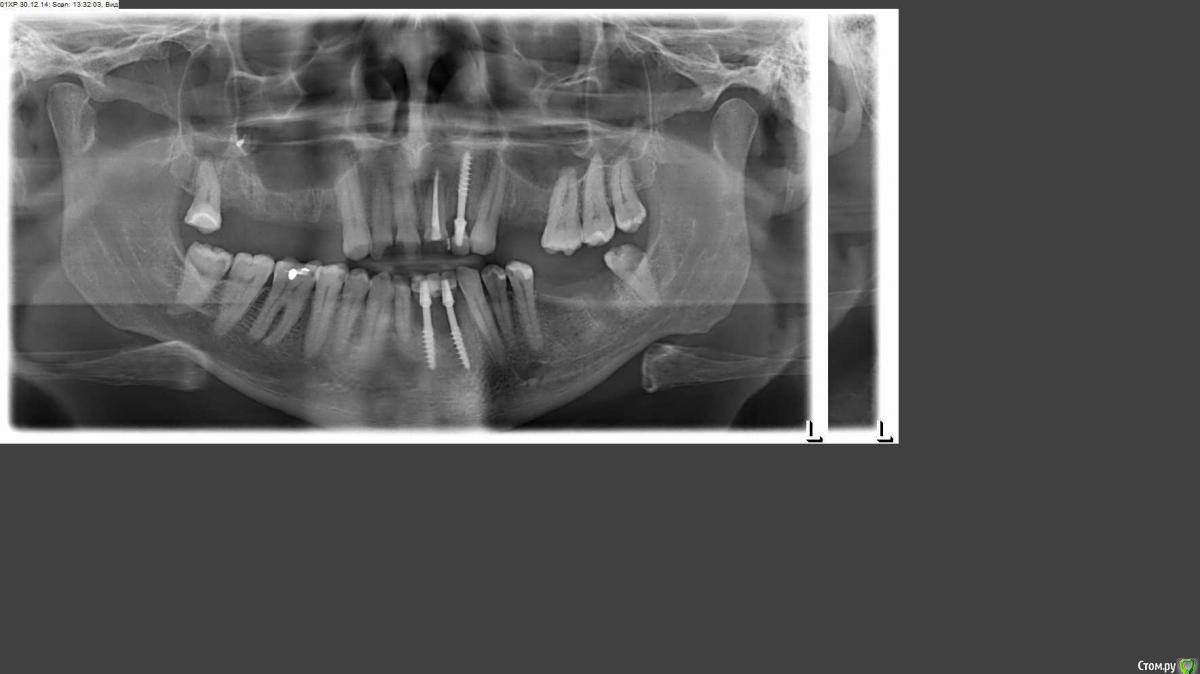

Trevor Опубликовано 24 января, 2015 Поделиться Опубликовано 24 января, 2015 Уважаемые учасники форума, скажите пожалуйста, что делают в случае, если часть наружного шва после синус-лифтинга отвалилась (8-ой день после операции), т.е. часть нитки с узлом на языке утром обнаружил? Остальные нити пока на месте, но нити не синтетические, и не шолковые скорее (как мне кажется), а обычные. Получается часть нити осталась в десне. Снимать швы будут 27-го, а операция была 15-го, т.е. на 12-ый день. Есть еще нюанс - операция была в другом городе, снимать, следовательно, будет другой хирург, не тот, что делал СЛ. Наверно нужно обязательно сказать, что часть нитей отвалилась уже? Может ли начаться нагноение если не всю нить удалить? Вообще допустимо ли использование не синтетических нитей?Стоят 3 импланта на месте 22, 32, 41 зубов. Прошло 4 месяца. Можно ли по снимку сказать как проходит остеоинтеграция и проходит ли вообще, объективно, не обращая внимание на систему этих имплантов? Учитывая весьма негативное отношение к этой системе на форуме в целом.Если бы я знал об этом раньше, я может и не стал ставить эти импланты. Но решение было принято раньше, чем я прочитал этот форум.снимок 30.12.14 импланты установлены 14.09.14 Ссылка на комментарий

diesel87 Опубликовано 25 января, 2015 Поделиться Опубликовано 25 января, 2015 А зачем открытый синус то делали? По поводу остеоинтеграции, лучше по прицельному снимку смотреть, но низ не нравится. Ссылка на комментарий

diesel87 Опубликовано 25 января, 2015 Поделиться Опубликовано 25 января, 2015 Ну как зачем? Во всех клиниках, в кот. был на консультации до этого, по плану был синусА что не нравится и чем, не могли бы Вы чуть подробнее?Судя по снимку можно было обойтись без открытого синуса Ссылка на комментарий